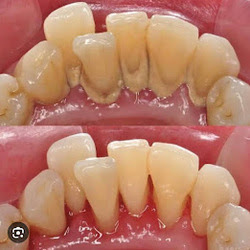

Welcome to our gallery

See how our company transforms ideas into reality. This gallery is a visual testament to our work and achievements.